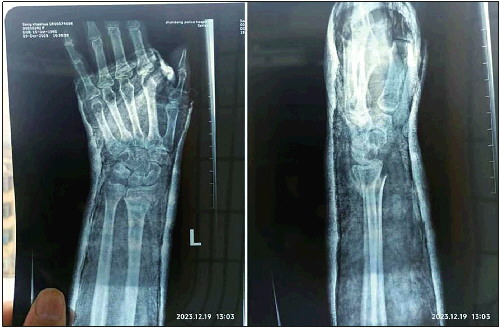

张秀梅上班途中滑倒,左手摔骨折。受访者供图